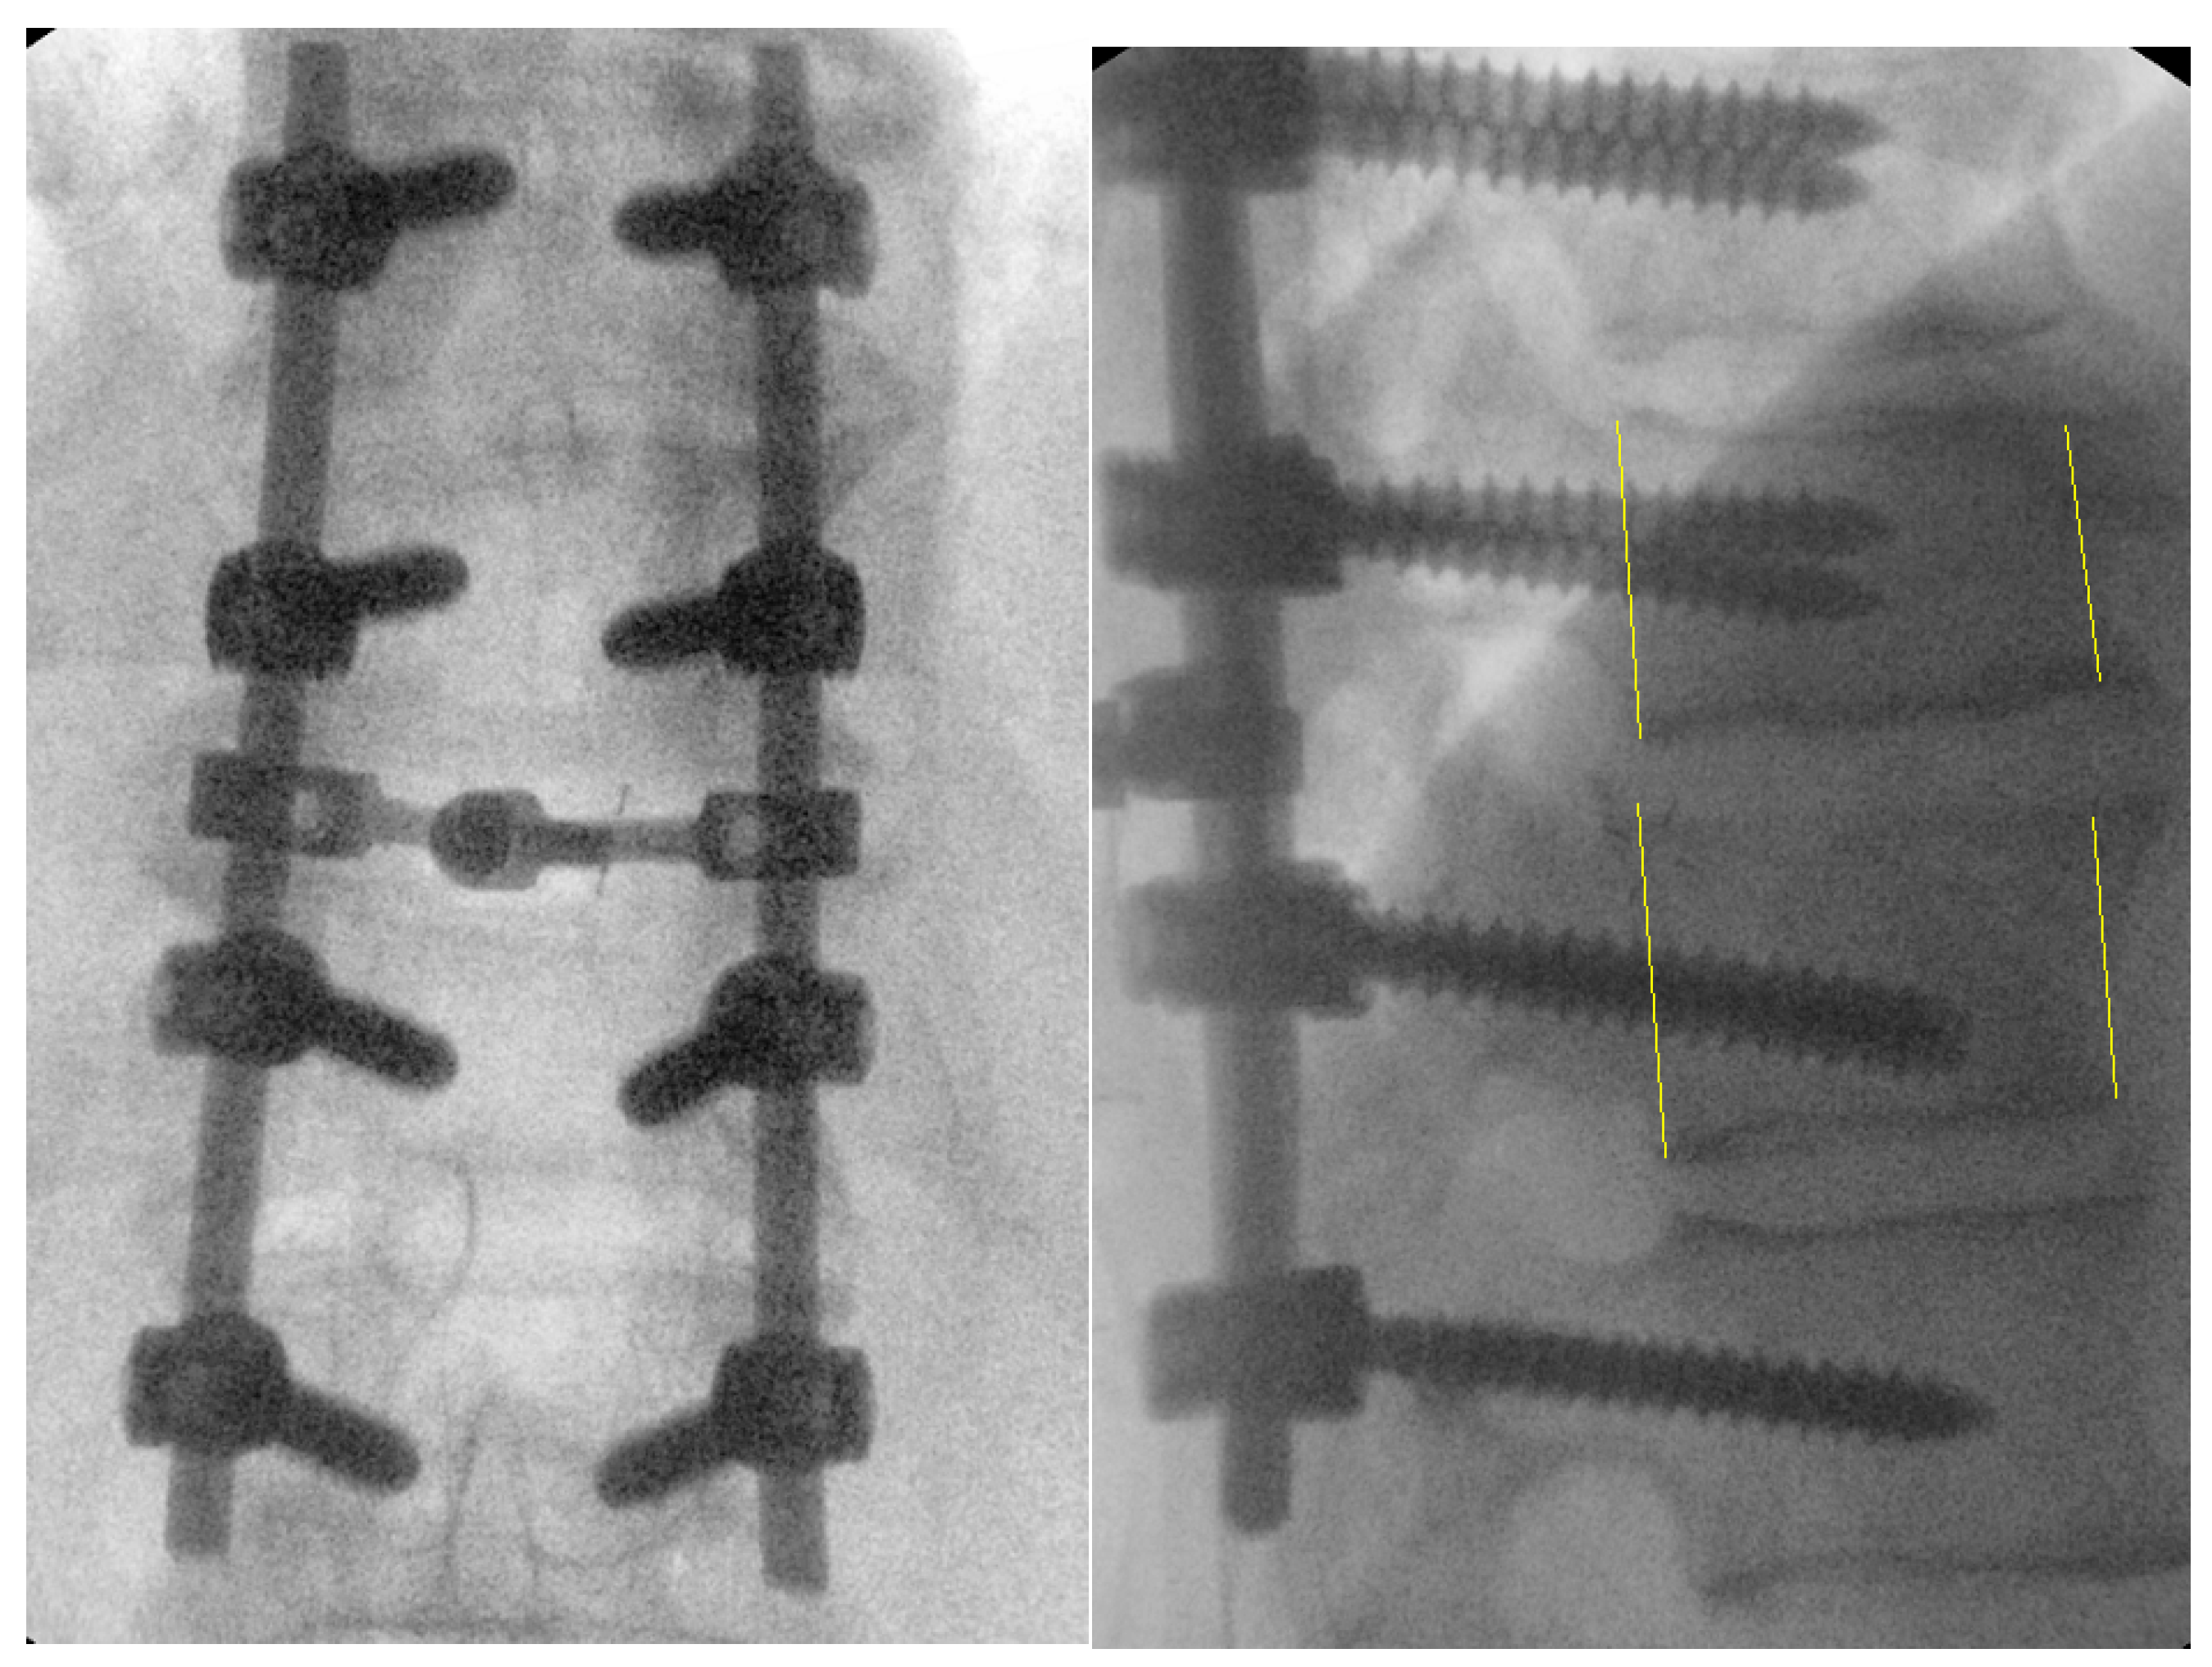

Figure 6.

Intraoperative fluoroscopic images after successful reduction, decompression, and posterolateral fusion of Th10-L1. Yellow lines represent the vertebral body height and the translation that is restored with the surgical fixation.